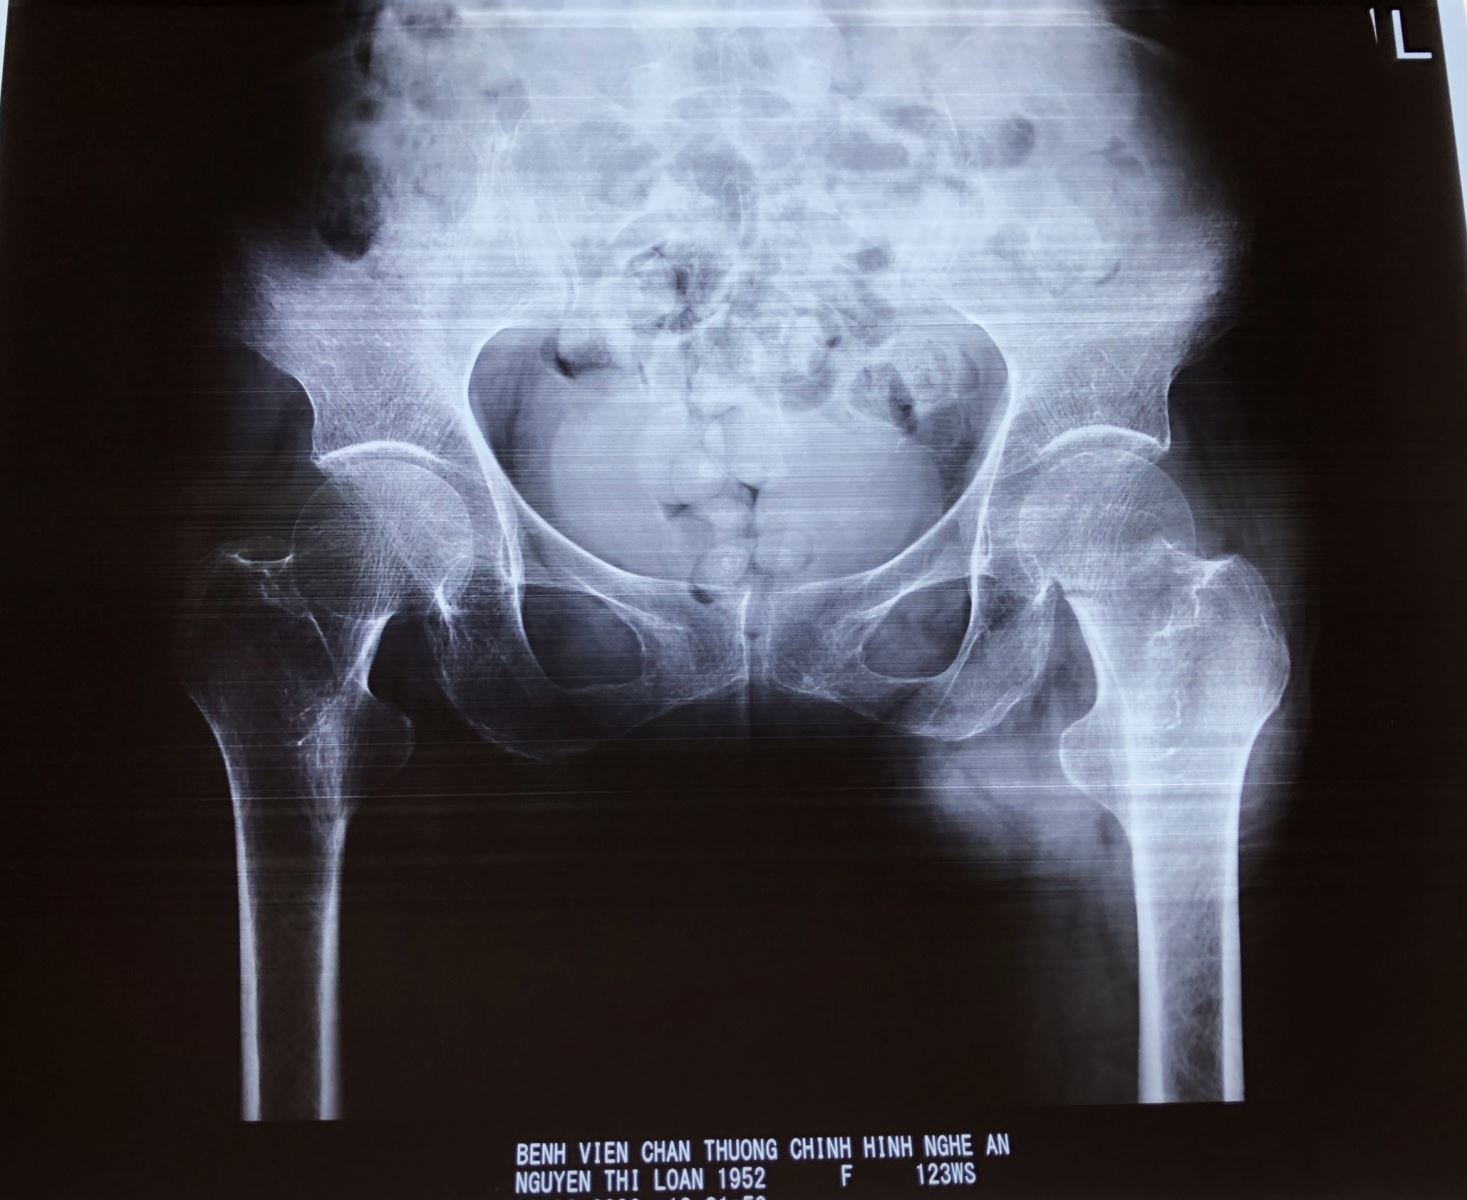

Hình ảnh phim chụp Xquang của bệnh nhân trước và sau phẫu thuật thay khớp háng

Bệnh nhân Nguyễn Thị Loan, 68 tuổi, ở TP.Vinh – Nghệ An có tiền sử parkinson, đã điều trị 6 năm nay. Đợt này bệnh nhân trượt chân ngã gây đau biến dạng, hạn chế vận động đùi háng trái. Vào Bệnh viện Chấn thương Chỉnh hình Nghệ An, bệnh nhân được chẩn đoán gãy cổ xương đùi trái.

Sau khi tiến hành hội chẩn, bệnh nhân được chỉ định phẫu thuật thay khớp háng bán phần. Ca phẫu thuật được tiến hành thành công bởi kíp mổ của ThS, Bác sĩ Nguyễn Hoài Nam – Giám đốc Bệnh viện và các cộng sự.